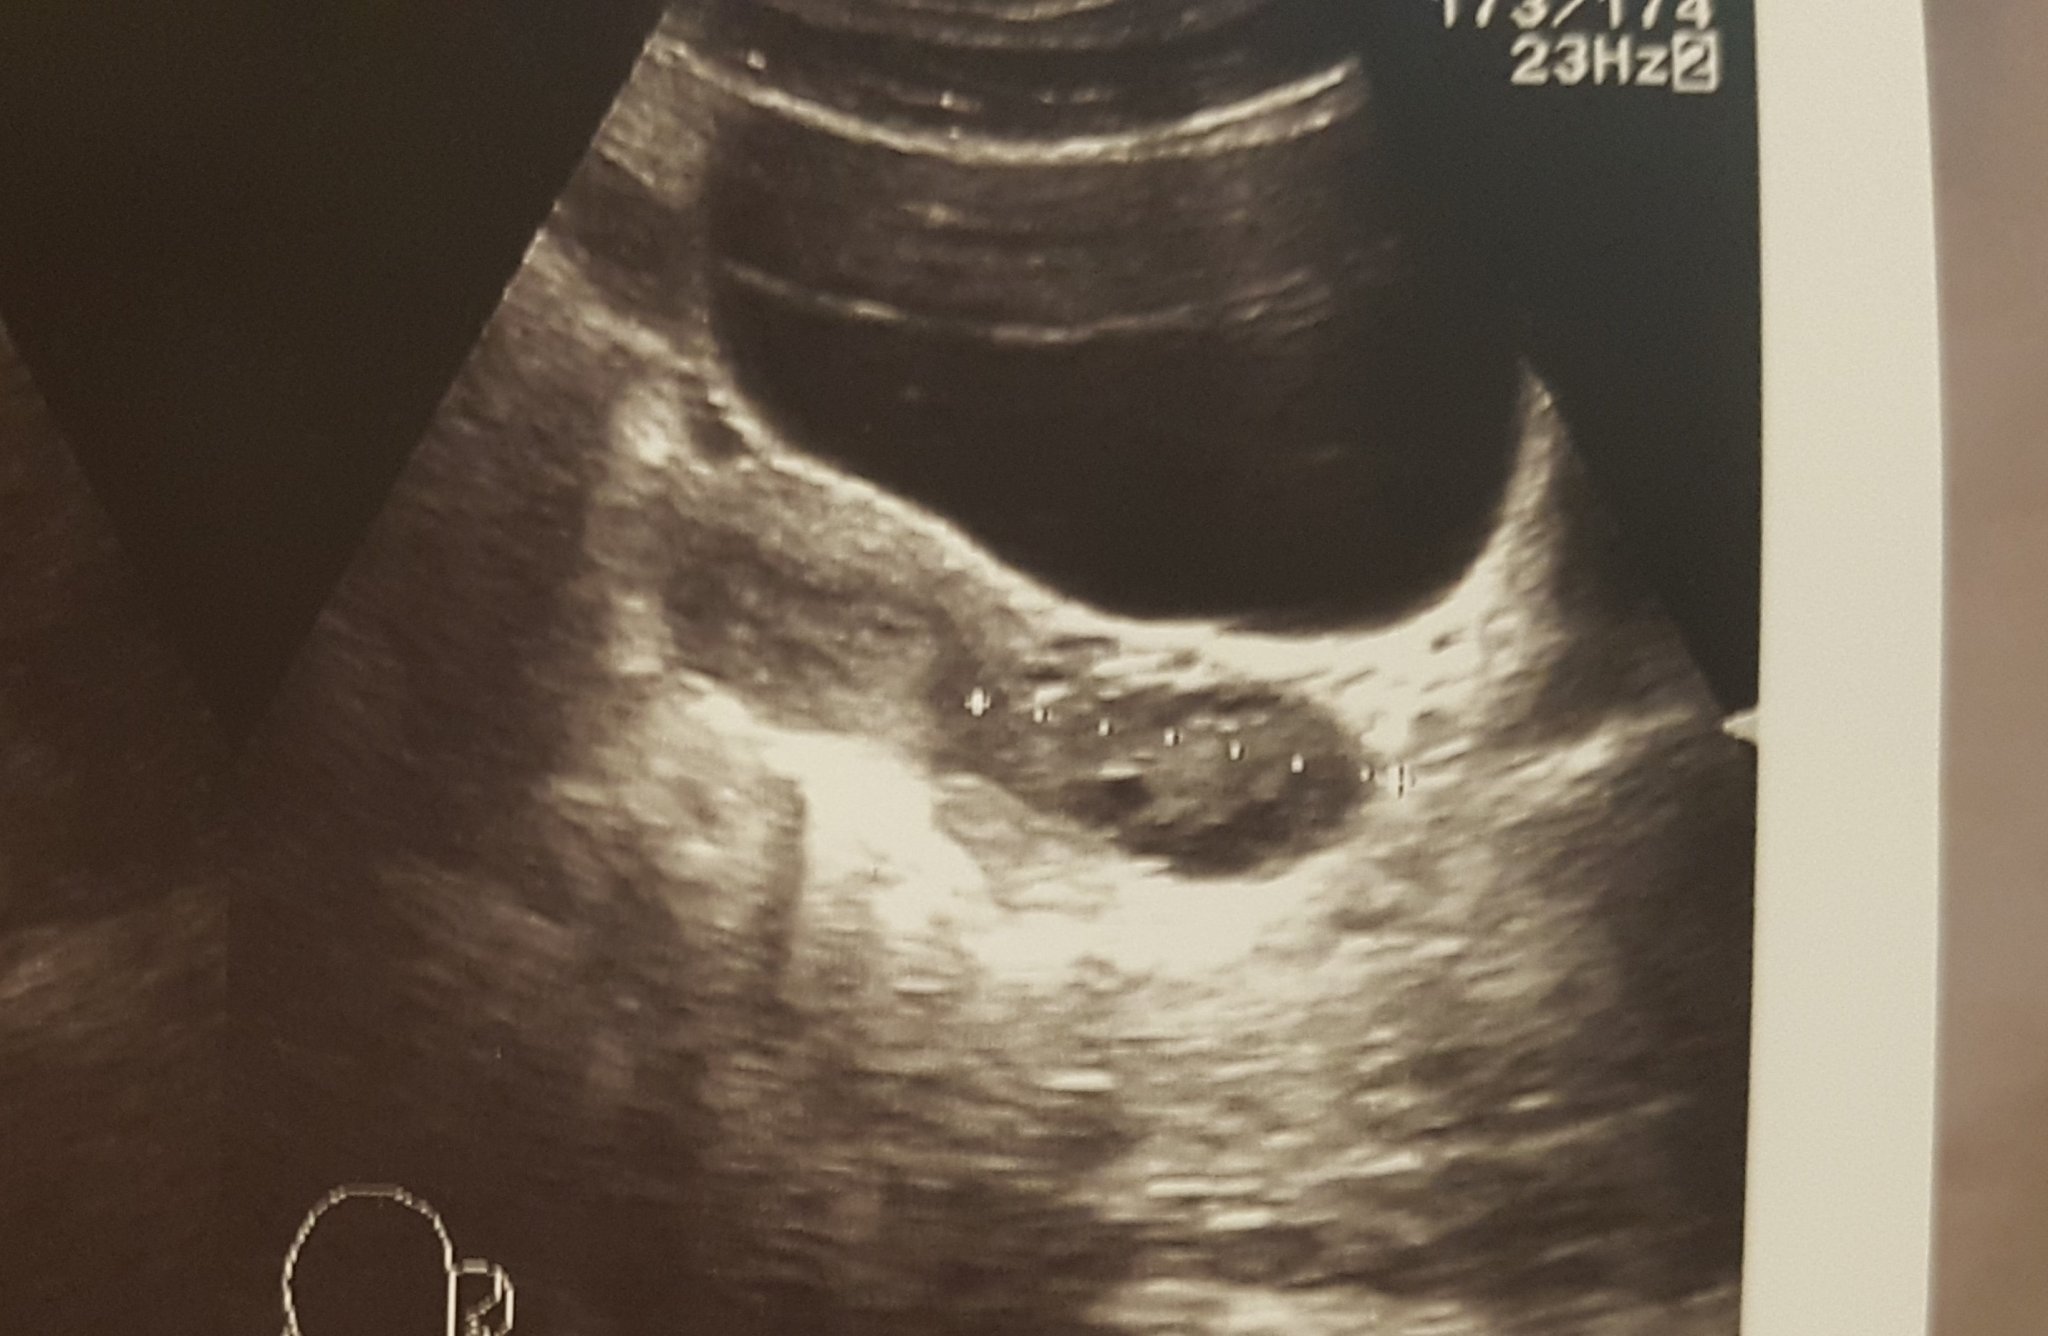

Момичета, някой сблъсквал ли се е с това от снимката? Единият лекар казва, че е киста и предписа противозачатъчни, другия каза, че няма нищо и всичко е ок. Аз все пак виждам това образувание до яйчника, преди съм имала, но бяха различни, бяха някак вътре в яйчника, а това е до него. Пускала съм туморни маркери, бяха в норма. Ще ходя и на трето мнение, но все пак, ако на някой му изглежда познато. Благодаря.

Дано не изръся някоя глупост, но ми прилича на ембрион. Простете ми, но точно така ми изглеждат първите месеци.

Прилича ми на киста. На твое място бих отишла на трето мнение.

На мен не ми изглежда като киста. Изчакай цикъла и след него направи нова ехография при добър Аг или специалист по образна диагностика.